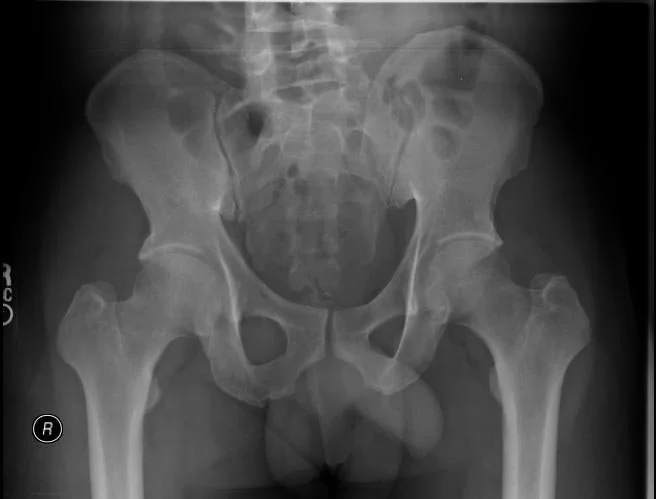

Minimally Invasive Deformity Surgery for Scoliosis

This surgical approach is to correct spinal curvature (scoliosis) using smaller incisions (versus traditional), muscle-sparing techniques, and specialized instrumentation. The surgery involves detailed imagery (x-ray, MRI, CT) to measure the spinal curves, identify rigid segments, and plan the screw placement. The patient is placed in a prone position on a radiolucent table with access to the spine .A small incision is made to the affected vertebrae, using specialized instruments and retractors to gently move muscles. Pedicle screws are inserted into the vertebrae, and rods are placed for the instrumentation segments, stabilizing the spine permanently. Incisions are then closed with minimal tissue disruption to reduce scarring and postoperative pain.

-

This surgery is done when conservative management with PT, medications and injections fail to resolve back and leg pain. It is done for adult and degenerative scoliosis and adolescent idiopathic scoliosis.

The include smaller incision, less tissue trauma, faster recovery and shorter hospital stay, reduced blood loss, effective correction and spinal stabilization, lower risk of infection and complications, and preservation of surrounding muscles and ligaments.

Typical hospital stay is 3-5 days, depending on the number of levels addressed. Patients begin walking the day after surgery. Physical therapy is initiated within a few weeks to restore strength and flexibility. Light activities can be resumed within 4-6 weeks, and more strenuous activity over 3-6 months. The fusion timeline is generally 6-12 months. Physician follow-up is needed to ensure proper hardware placement and spinal alignment.